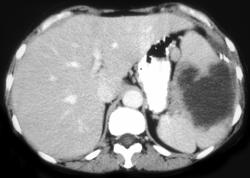

Splenic Abscess